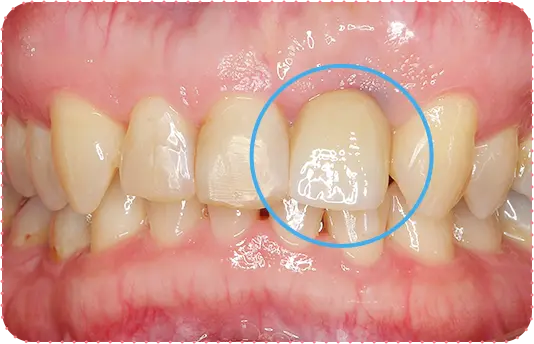

Before

After

主訴

上の前歯が長くて気になる

治療期間

9か月

治療費

30万円

治療内容

右上1番を小矯正治療にて歯茎を増やし、右上1番と左上1番をセラミッククラウンにて修復

治療のリスク

咬み合わせによっては、セラミックが欠ける可能性があります。